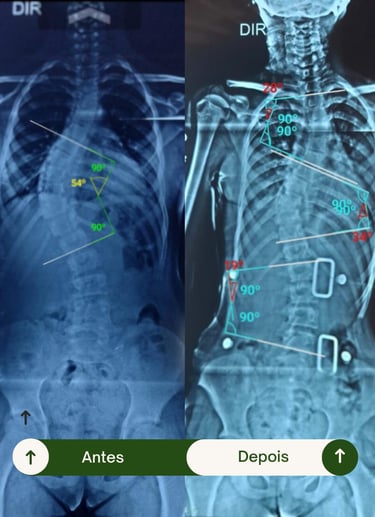

Resultados Comprovados

Transformando vidas por meio da fisioterapia e da tecnologia 3D.

Veja como nossos pacientes reconquistaram mobilidade, conforto e confiança.